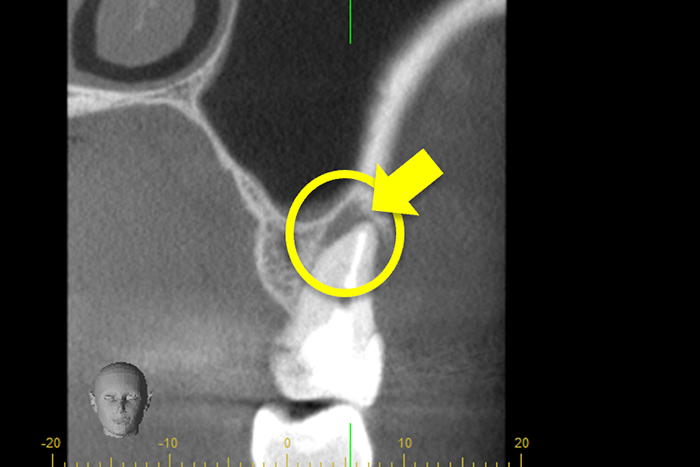

更に、拡大すると歯根破折に加え、器具の破折片も確認できる。

| 治療費 | 破折ファイルの除去費:16,500円 |

| 治療内容 | 破折ファイルの除去 |

| 治療のリスク | 抜歯の可能性 |

| 主訴 | 破折器具除去依頼 |

| 治療期間 | 1回 |

| 治療費 | 38,500円 |

| 治療のリスク | 除去できない・パーフォレーション |